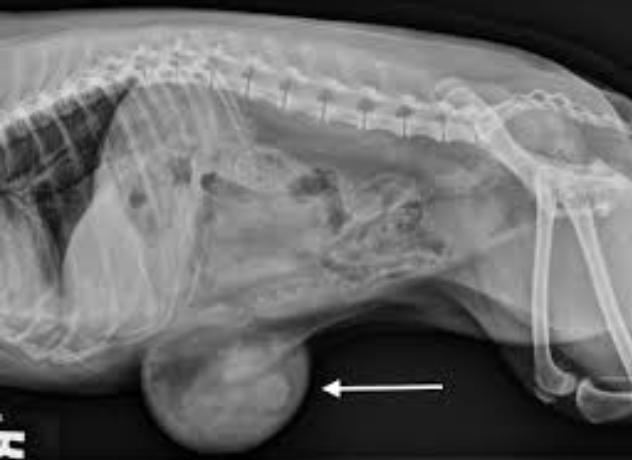

因疝气存在于腹内,兽医可能会建议患犬进行X光检查以评估患犬的状况。如若确定以手术为修复脐疝的手段后,兽医会让患犬进行麻醉测试,确保患犬能够接受麻醉程序。

根据主人主诉患犬情况,再结合X光结果确定腹部任何组织后,可确诊为脐疝。